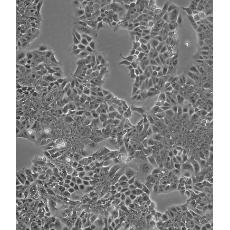

HCT-15 [HCT15]

產(chǎn)品名稱 HCT-15 [HCT15]

中文名稱 人結(jié)直腸腺癌細胞

組織來源 結(jié)腸腺癌;男性

細胞種屬 Homo sapiens, human

生長特性 adherent

形態(tài)特征 epithelial

細胞描述 HCT-15 cells are CSAp negative(CSAp-).The cells are positive for keratin by immunoperoxidase staining.